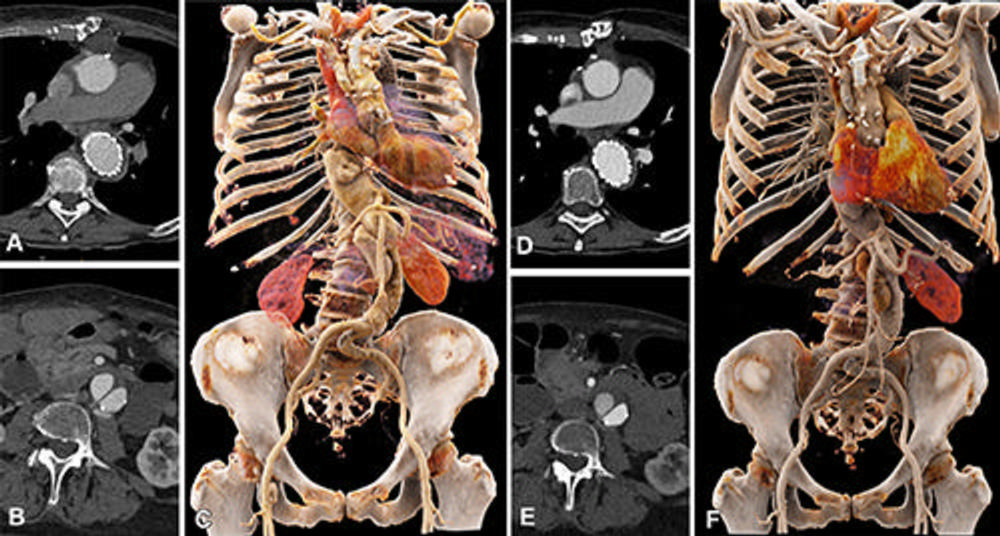

Figure 5. Comparison of image quality between EID CT with standard contrast media protocol and PCD CT with low-volume contrast media protocol using a matched radiation dose. Transverse and three-dimensional cinematic rendered images from thoracoabdominal CTA in a 71-year-old woman in group 2 are shown. (A–C) Images from third-generation EID CT with automated tube voltage selection of 90 kVp. (D–F) Images from PCD CT with reduced contrast media volume of 52.5 mL and VMI at 50 keV. Time interval between scans was 6 months. CTA = CT angiography, EID = energy-integrating detector, PCD = photon-counting detector, VMI = virtual monoenergetic images.